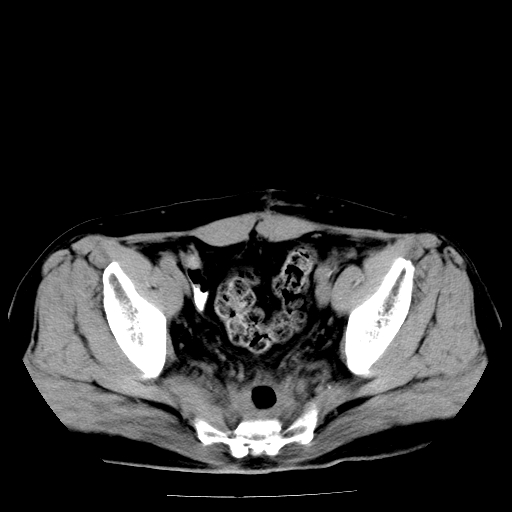

男,66岁,直肠癌术后一个月,化疗前ct检查。

直肠癌造瘘术后改变,周围淋巴结转移

直肠癌造瘘术后改变,盆腔多发淋巴结转移

直肠壁厚,盆腔多发淋巴结转移.

直肠癌造瘘术后改变,直肠周围软组织增厚,盆腔多发淋巴结转移。前列腺肥大。

结肠造瘘术后。

直肠癌周围浸润。

盆腔内有很多点点,可能是淋巴结转移,建议增强。“直肠周围浸润”无法与术后斑痕鉴别,治疗后再说

直肠癌造瘘术后改变,直肠周围软组织增厚,盆腔多发淋巴结转移。前列腺肥大